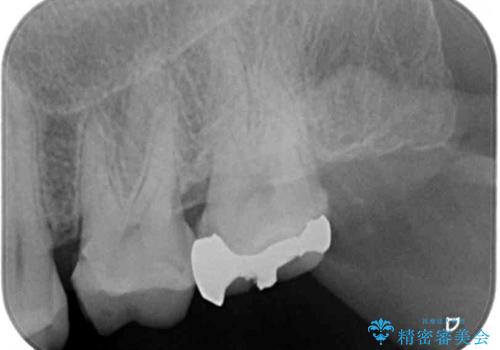

- 近医にて、銀歯の周りの歯が欠けてむし歯のようになっていると言われたとのことで来院された患者様です。

非常に咬合力が強く、銀歯やセラミックのような堅い素材では歯にダメージがかかり、治療を繰り返す可能性が高いと思われたので、ゴールドインレー(白金加金インレー、PGAインレー)にて、治療中の歯と銀歯が装着されている歯を修復治療することとしました。